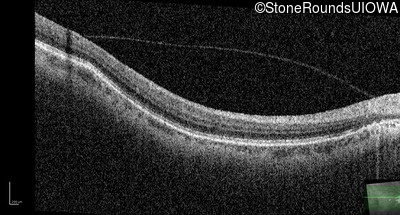

Age at visit: 32 years